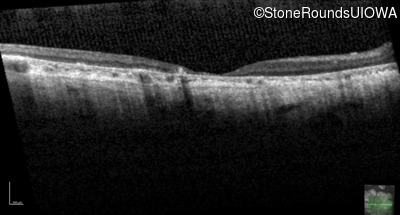

| AR Stargardt Disease | ABCA4 | Cys205Phe TGC>TTC | Gly863Ala (G)GA>(G)CA | AR |